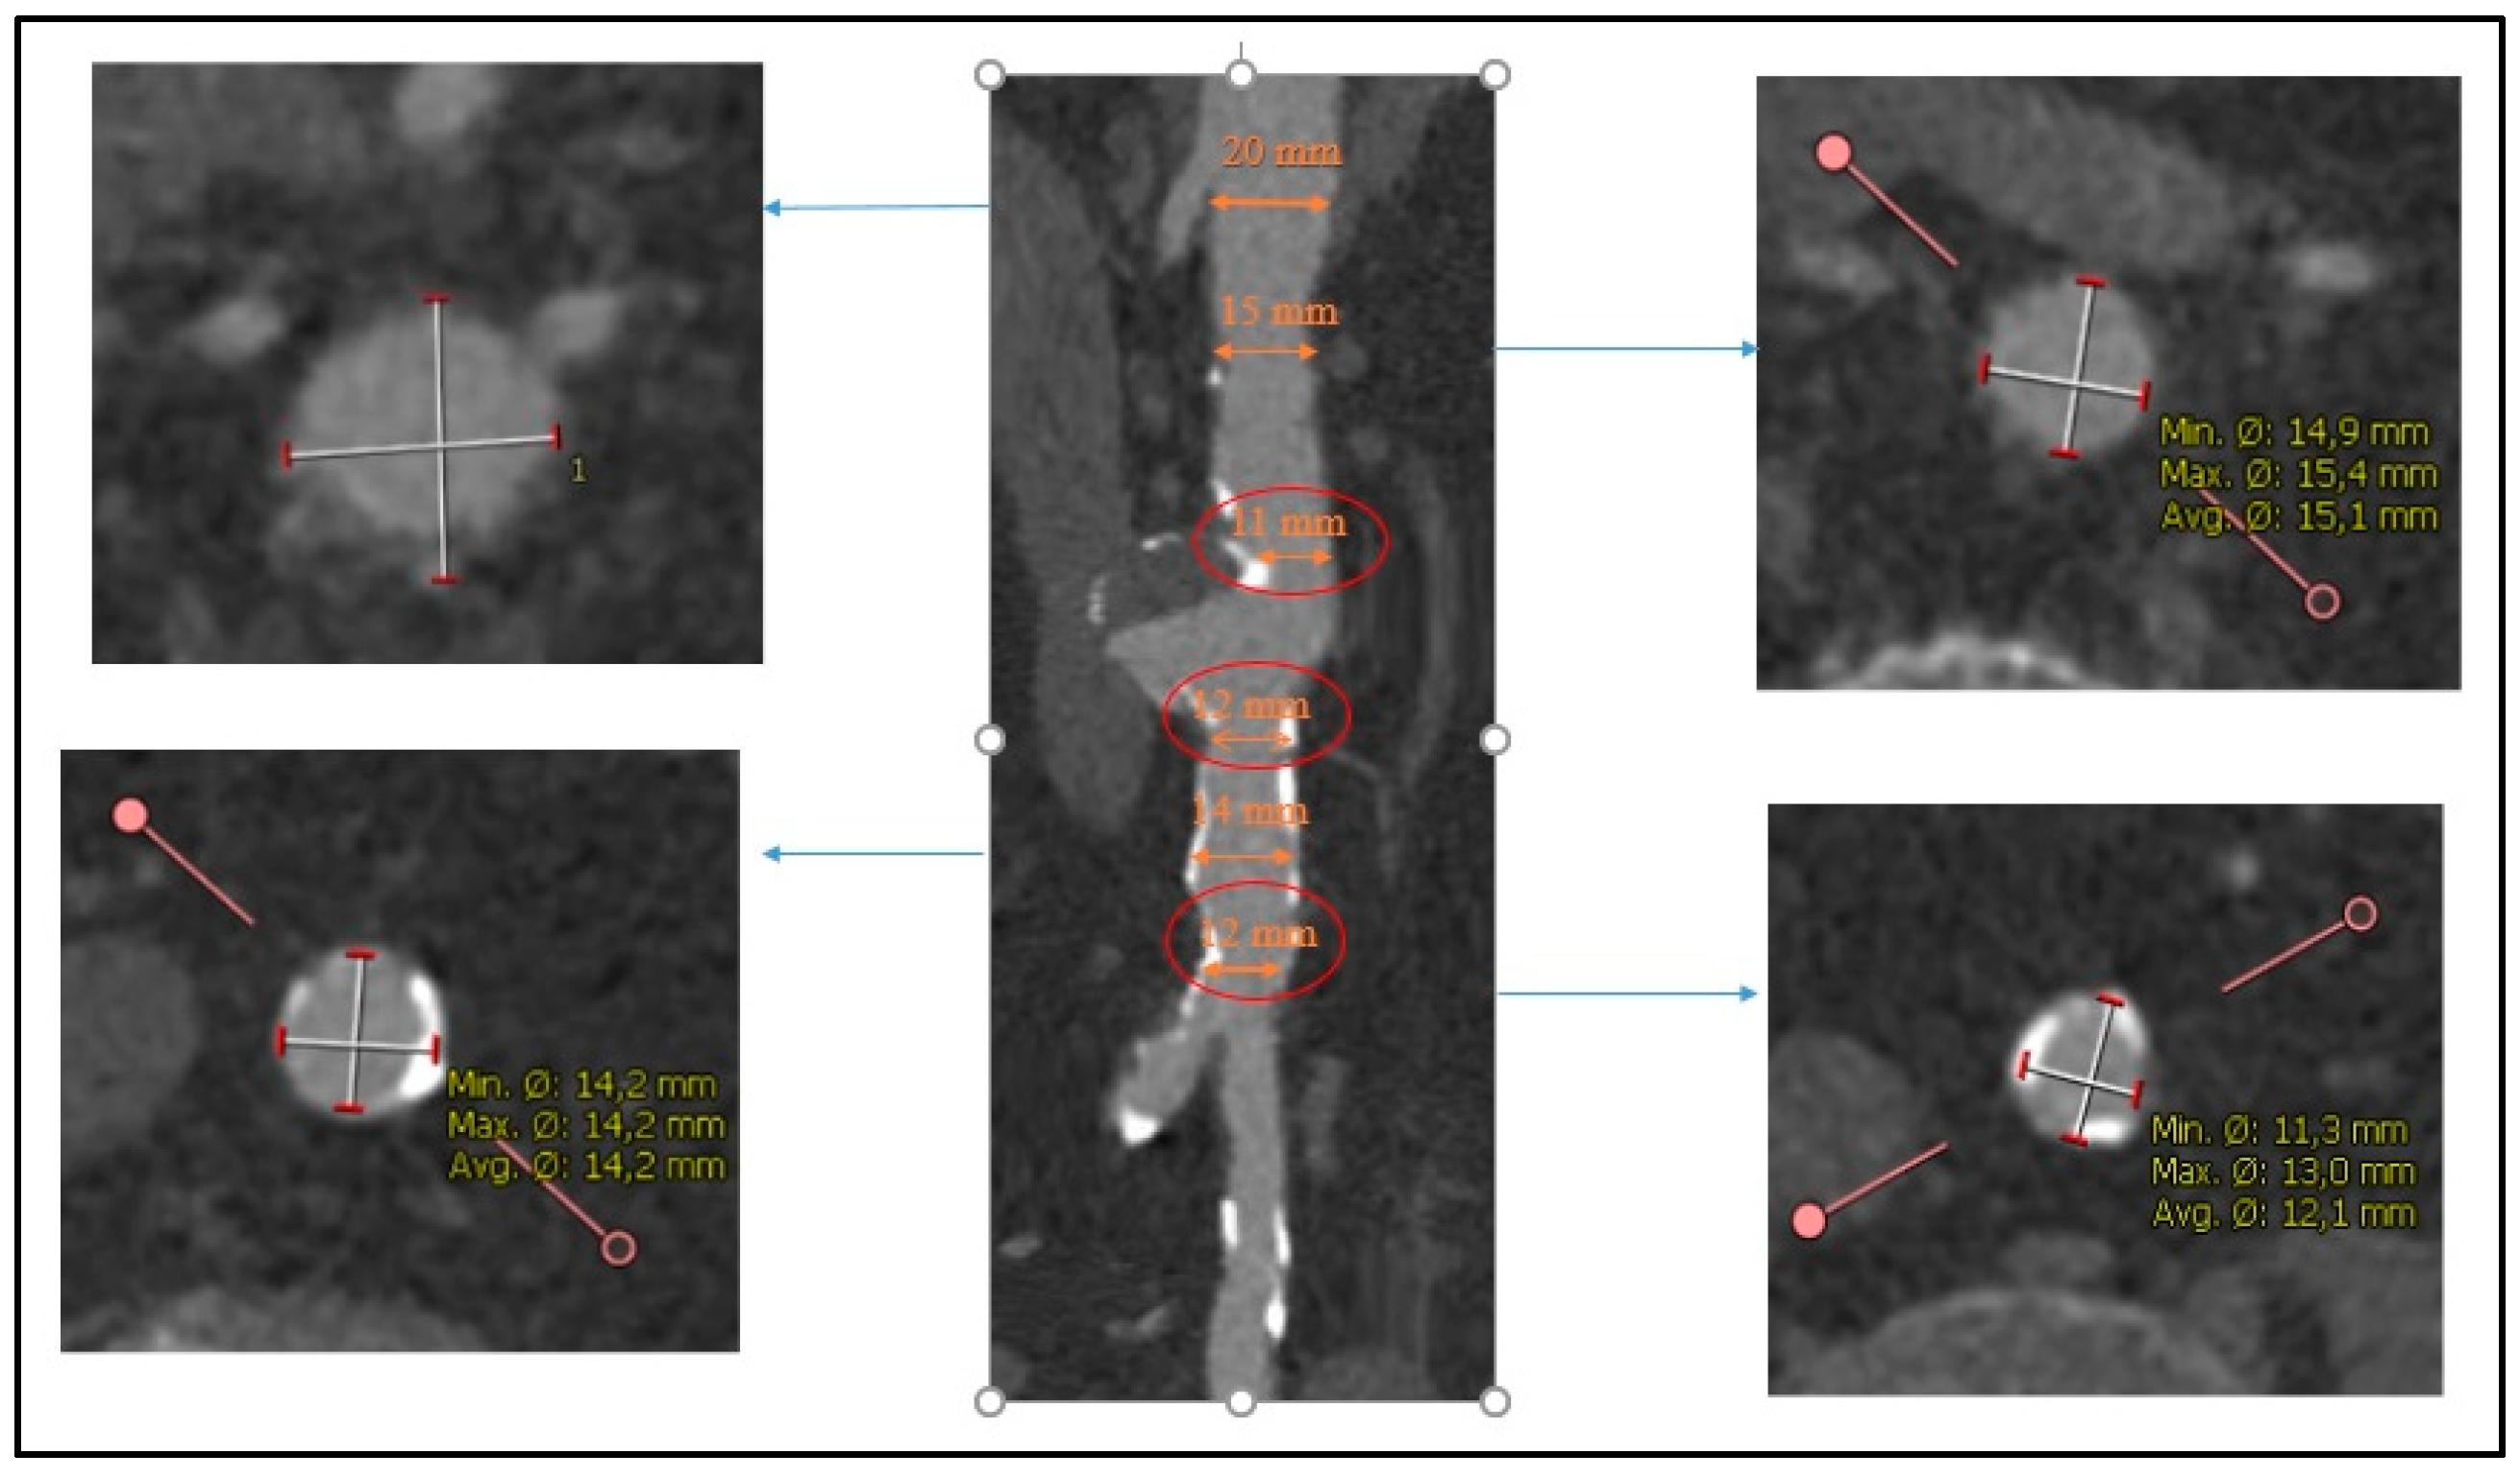

4.1. Infrarenal EVAR